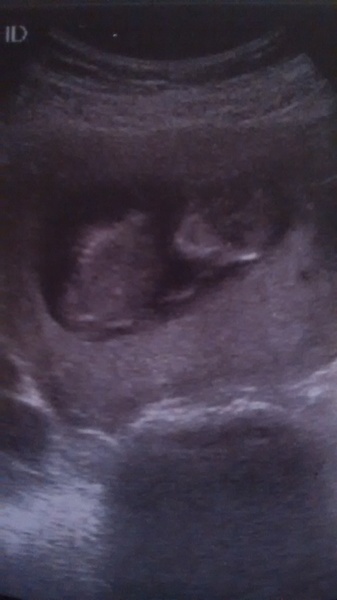

MissisBee · 02/12/2016 12:45

Here's my pic. All went well this morning. Turns out my midwife also delivered my friend's baby on Tuesday! Good luck to all with scans coming up

Aww congratulations Missis. Lovely pic, glad it went well x

Lovely scan Bee

Lovely pic missis!

Congrats on your scan today Miss!